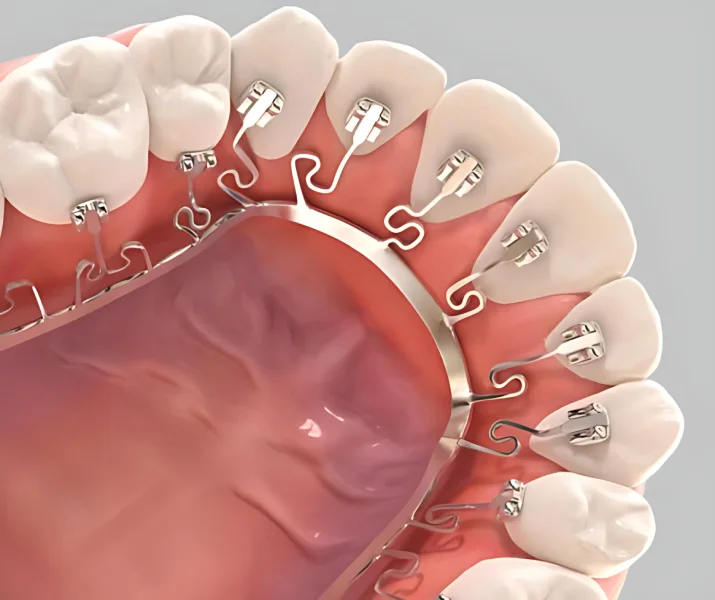

จัดฟัน Brava AI คือการจัดฟันที่ซ่อนเครื่องมือไว้ด้านในของฟันที่มองเห็นได้จากด้านนอก และมองไม่เห็นอุปกรณ์ที่ใช้จัดฟันเมื่อยิ้ม การจัดฟันแบบ Brava AI แตกต่างจากการจัดฟันแบบโลหะทั่วไปตรงที่ ใช้เทคโนโลยีขับเคลื่อนฟันด้วย AI ฟันทุกซี่ไม่ได้เชื่อมต่อกันโดยตรงจากลวดจัดฟัน แต่เป็นเชื่อมต่อกันผ่านอาร์ม NiTi ที่ยืดหยุ่นและแข็งแรงซึ่งถูกออกแบบด้วยกระบวนการ Finite Element Analysis (FEA) ที่ซับซ้อน

โดยอาร์ม NiTi จะยื่นออกมาจากแกนบาร์โลหะที่เป็นวัสดุโลหะจำรูป (เป็นวัสดุชนิดเดียวกันกับที่ใช้ในอุตสาหกรรมอวกาศ) ทำให้ NiTi แต่ละชิ้นนั้นจะส่งแรงที่เหมาะสมในการเคลื่อนฟันแต่ละซี่ ทำให้การเคลื่อนที่ของฟันแต่ละซี่นั้นเป็นอิสระจากฟันซี่อื่น ๆ ไม่ส่งผลกระทบกันและกัน

Brava อาศัยหลักการที่เรียกว่า “Independent Movers” หรือการเคลื่อนฟันอย่างเป็นอิสระ

เครื่องมือจัดฟันจะถูกยึดด้วยแกนบาร์ทรงโค้งที่ถูกออกแบบมาให้พอดีกับรูปปาก ซึ่งแกนบาร์นี้ทำหน้าที่เป็นจุดยึดที่มั่นคง

แขนกลขนาดเล็กที่ทำจากวัสดุโลหะจำรูป (Nitinol) ซึ่งมีคุณสมบัติยืดหยุ่นและแข็งแรง จะยื่นออกมาจากแกนบาร์และยึดติดกับฟันแต่ละซี่อย่างอิสระ

แขนกล (NiTi Arms) แต่ละชิ้นจะส่งแรงที่คำนวณไว้ล่วงหน้าไปยังฟันแต่ละซี่อย่างต่อเนื่องและเป็นอิสระต่อกัน ทำให้ฟันสามารถเคลื่อนที่ได้พร้อมกันโดยไม่ส่งผลกระทบต่อซี่อื่น